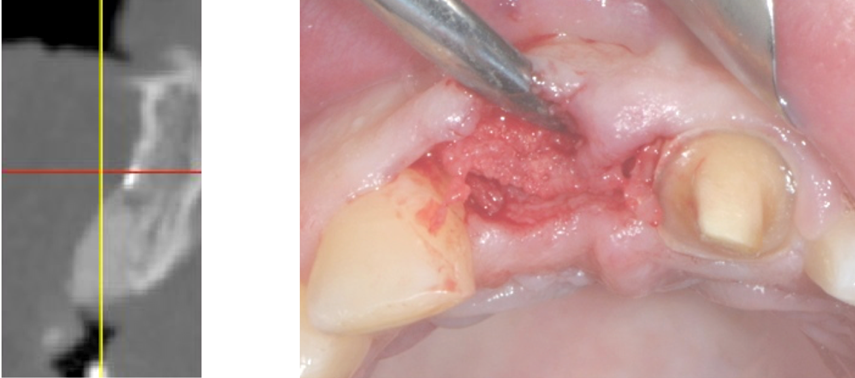

Immagine clinica e radiografica al momento della rimozione della membrana

Inserimento implantare dopo quattro mesi